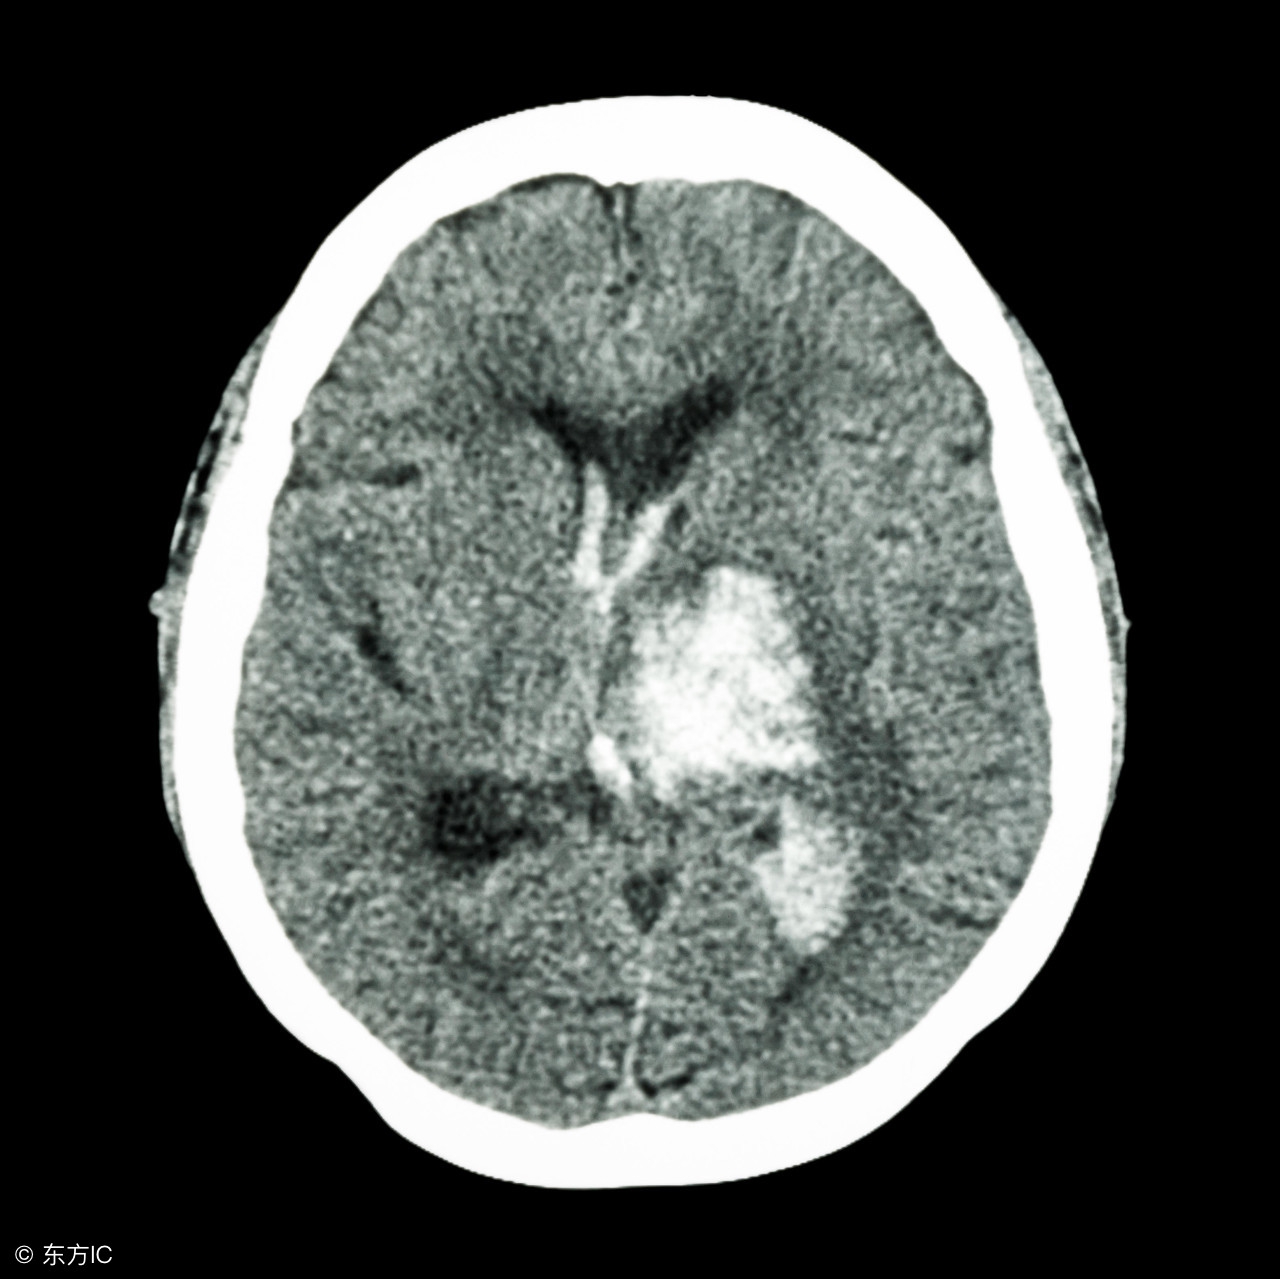

高血压脑出血手术后的饮食